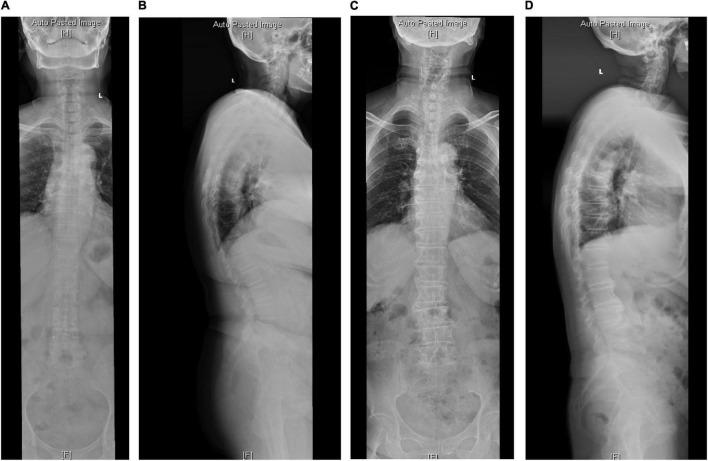

退行性脊柱后凸患者不同矢状面参数之间的相关性

Correlation Between Different Sagittal Parameters in Patients With Degenerative Kyphosis.

To explore the relationship between different sagittal parameters and identify the fitting formula of spino-pelvic parameters in patients with degenerative kyphosis (DK).

SUMMARY OF BACKGROUND

Sagittal balance is increasingly recognized as a predictor of clinical outcomes in patients with DK, while the relationship between different sagittal parameters in patients with DK remains unidentified.

METHODS

A retrospective study with 279 participants was conducted. There were 168 DK patients which were divided into a sagittal balance group (SB:52 cases) and sagittal imbalance (SIB:116 cases). Radiographic measurements included thoracolumbar kyphosis (TLK), lumbar lordosis (LL), thoracic kyphosis (TK), pelvic incidence (PI), and pelvic tilt (PT). The correlations were analyzed between different sagittal parameters.

RESULTS

There were significant differences between the SB and SIB groups in terms of TLK, LL, PI-LL, PT, SVA, sacral slope (SS), and TK. For patients with DK, the LL was correlated with PT and TK. The linear regression was LL = 22.76-0.28 × PT + 0.62 × TK. In the SB group, TK was the influencing factor for LL and the linear regression analysis showed that LL = 33.57 + 0.33 × TK. While in the SIB group, PT and TK were in synergistic effect with PI-LL, the linear regression analysis showed that LL = 22.76-0.28 × PT + 0.62 × TK.

CONCLUSION

From the present study, we can see that LL has a significant correlation with PT and TK in patients with DK, while in SB, the LL was only correlated with TK. Therefore, the correction of LL in a different group should be calculated to avoid the incidence of proximal junction kyphosis (PJK).